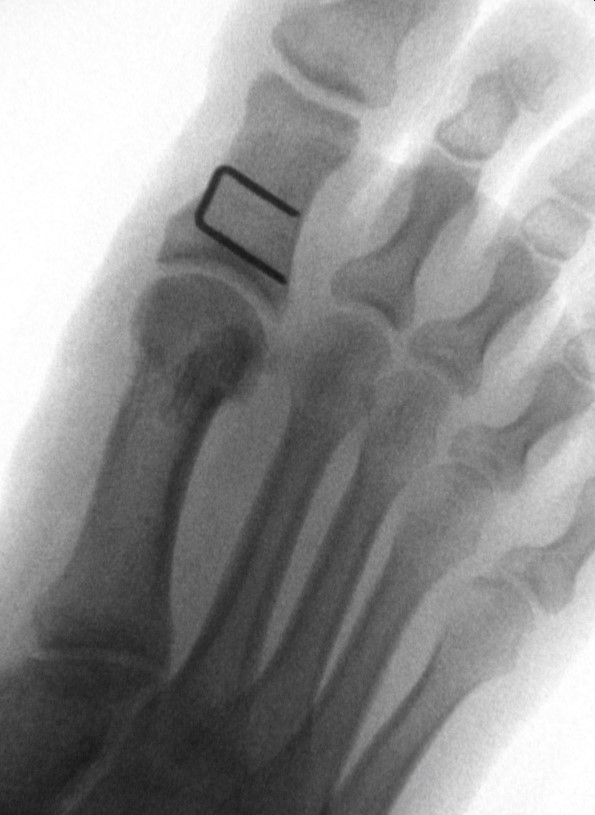

Autofahren Nach Hallux Op. Hallux valgus OP Erfahrungen, Methoden & Behandlung Wie lange kann man nach Hallux OP nicht Gehen? Nach einer Operation dauert es etwa 4 bis 6 Wochen, bis die Knochen stabil genug sind, um den Fuß wieder voll zu belasten. Der genaue Zeitpunkt hängt von der Art des Eingriffs und dem betroffenen Fuß ab

Nach minimalinvasiver Hallux Op kann man sogar nach 3-7 Tagen normale Schuhe anziehen. Wann wieder Autofahren nach Hallux rigidus OP? Nach einer Hallux-rigidus-Operation können Sie das Autofahren wieder aufnehmen, sobald der Fuß vollständig belastbar ist und Sie die Pedale sicher und schmerzfrei bedienen können

Was Sie über das Autofahren nach einer Operation wissen müssen, erfahren Sie in diesem Artikel. Wann kann ich nach der Hallux OP wieder Autofahren? Grundsätzlich können Sie unmittelbar nach der Hallux Valgus Operation Autofahren Nach minimalinvasiver Hallux Op kann man sogar nach 3-7 Tagen normale Schuhe anziehen.

Hallux valgus OP Erfahrungen, Methoden & Behandlung. Wie lange kann man nach Hallux OP nicht Gehen? Nach einer Operation dauert es etwa 4 bis 6 Wochen, bis die Knochen stabil genug sind, um den Fuß wieder voll zu belasten. Im Fall einer Hallux OP können Sie grundsätzlich unmittelbar danach Autofahren